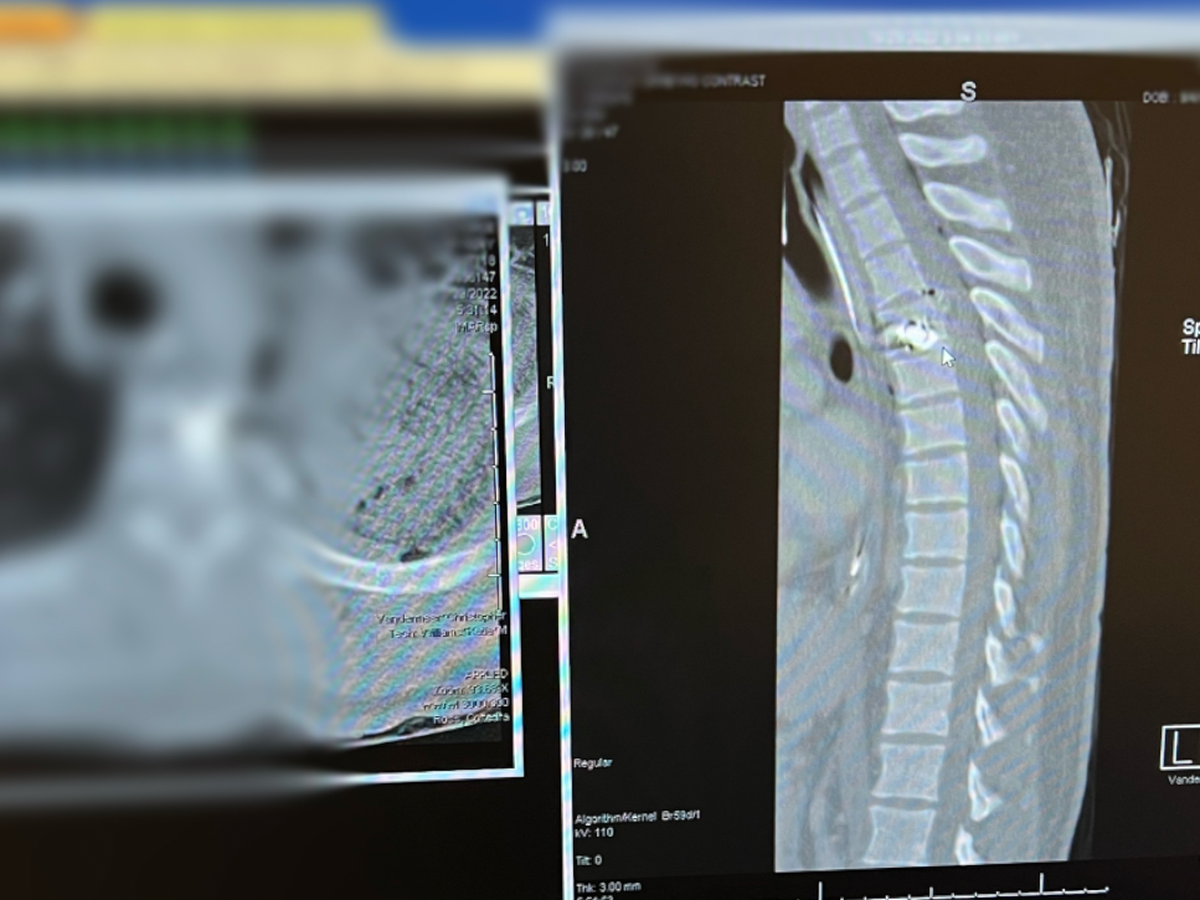

Senseless gun violence is such a huge problem and unfortunately I became a victim to it. I was shot 4 out of 6 shots fired and was lifeless when responders arrived. I had to be revived, airlifted to Atrium in Charlotte, undergo multiple lifesaving surgeries, and have numerous blood transfusions. I was in critical condition and my body fell into a coma. Due to one of the bullets being lodged in my spinal cord (T-4 fracture) I am now paralyzed from the nipple line down.